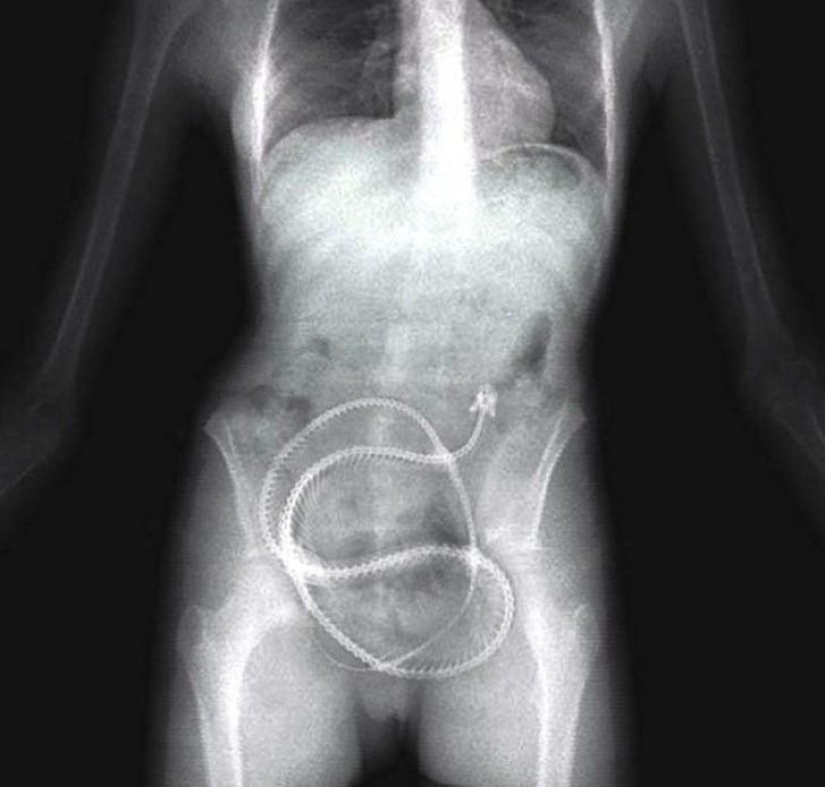

22. Surgical forceps.

24. Scissors.